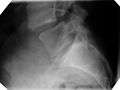

| X-ray of the lateral lumbar spine with a grade III spondylolisthesis at the L5-S1 level. | |